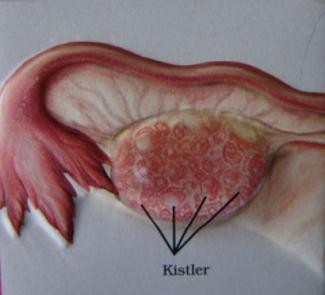

- Stein ve Leventhal adlı bilim adamları tarafından ilk olarak tarif edildiği kabul edilir (“Stein-Leventhal Sendromu...